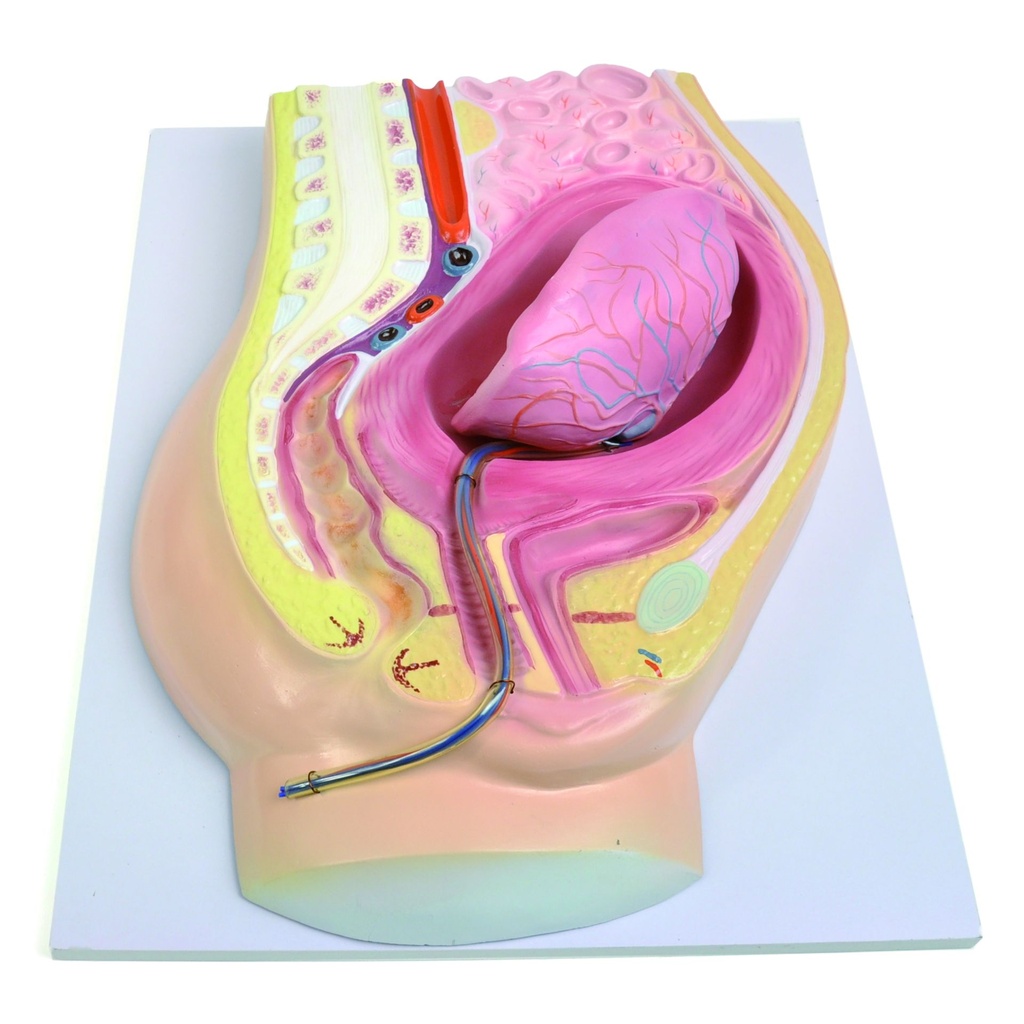

Detailed models for medical training

In our range you will find numerous models from HeineScientific for both human medicine and the veterinary sector. These include individual body parts, organs, complete body structures or dental models. They can be used to illustrate and teach diseases and functions.